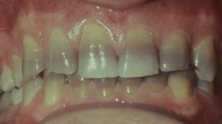

from use during tooth development; may also discolor skin, sclera, thyroid; RX for acne, cystic fibrosis, RA

tetracycline staining

tetracycline